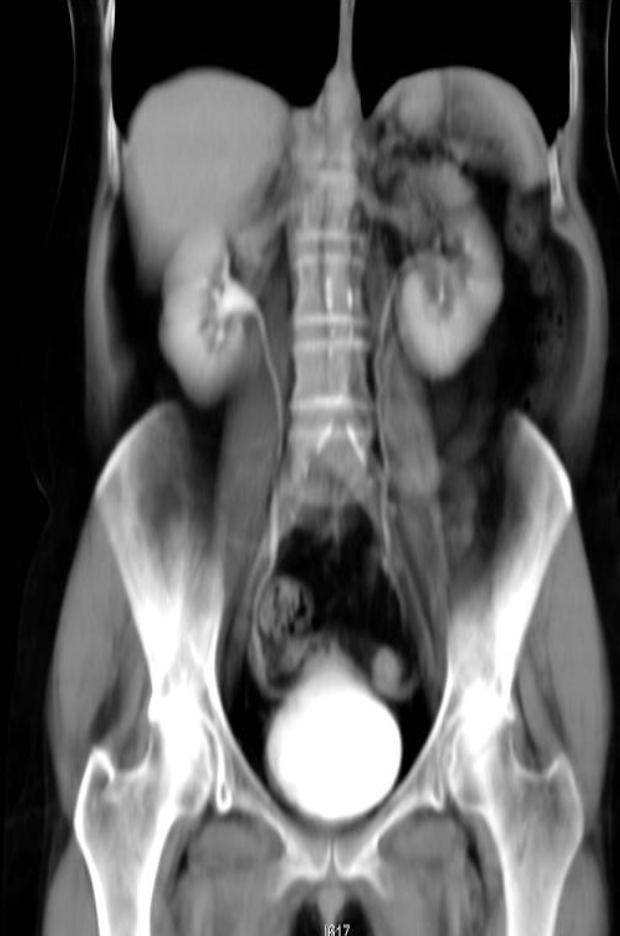

A. Give the name of the imaging examination in the given image. CTU

B. Give the NAMES of the used contrast media for the examination Iodide Contrast Media

Abdominal CT with IV contrast , coronal section

Hyperdense calculi located in the proximal third of the left ureter. As a result, the proximal ureter and the renal pelvis are dilated.